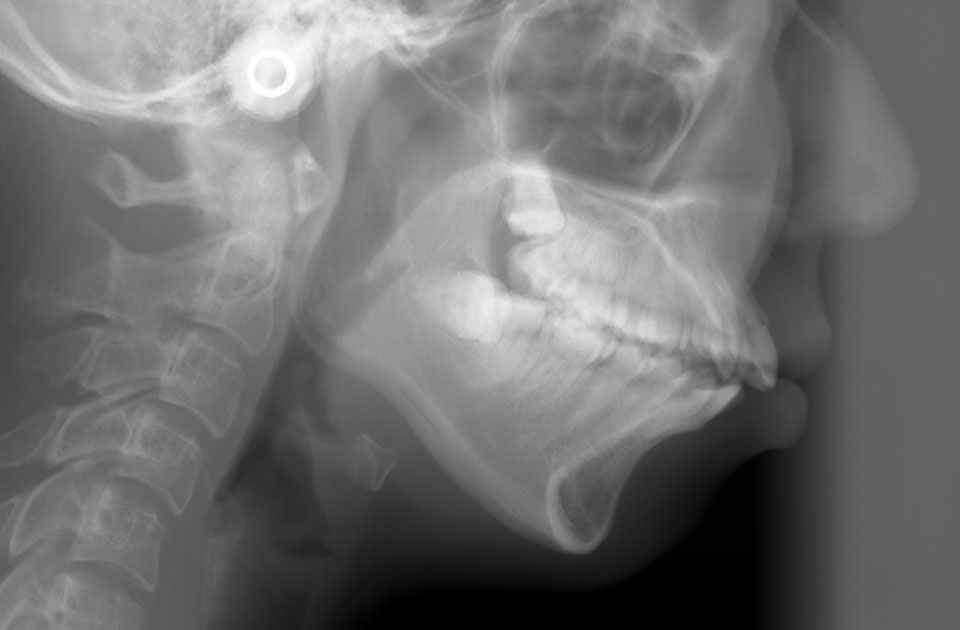

矯正前 レントゲン

矯正後 レントゲン